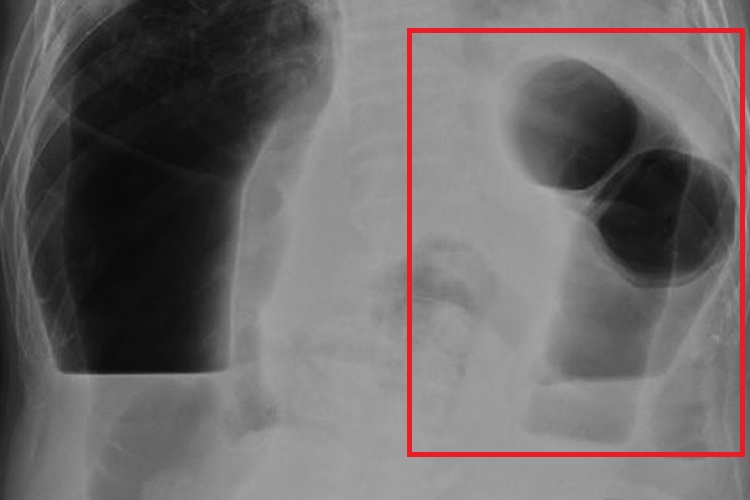

结肠梗阻仰卧位腹平片上表现为梗阻部位以上结肠充气扩张,被液体所充填,位于腹部周围,可显示出结肠袋借以与小肠区别,在站立位片上可见结肠内有宽大的气液平面。